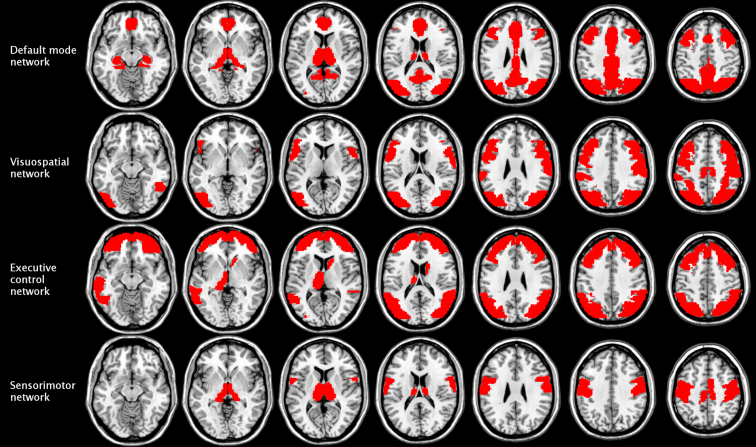

Classification performance proved to be more sensitive to the occlusion of large-scale brain networks. When trained solely on the in-house dataset (ConvTrainFullTrain), the CCNN seemed to rely heavily on the connectivity pattern of the default mode network, whose occlusion resulted in a 12.3% drop in accuracy (Fig. 2, right panel). In contrast, when the network was trained on the public dataset only (ConvConstFullConst), the regions of the visuospatial network turned out to be crucial for classification, as the occlusion of these regions resulted in below-chance performance (56.1%; Fig. 2 left panel). The visuospatial network remained highly important when the CCNN was fine-tuned to the in-house dataset, along with the executive control network in the ConvInitFullInit condition (8.8% drop in accuracy; Fig. 3, left panel) and the sensorimotor network in the ConvInitFullTrain condition (10.5% drop in accuracy; Fig. 3, right panel). The regions corresponding to these networks are shown in Fig. 4.

Figure 4:

Functional brain networks that strongly contributed to classification by age group performed on the in-house dataset in the baseline and transfer learning conditions. These networks were defined by mapping the constituent functional ROIs identified by Shirer et al. [32] onto the anatomical ROIs in the Harvard-Oxford Atlas. The importance of each network was assessed by occluding the connectivity fingerprints of the constituent ROIs in the input correlation matrices and examining the resulting change in performance when the network classified the in-house exemplars using the weights and biases established in the ConvConstFullConst, ConvTrainFullTrain, ConvInitFullInit, and ConvInitFullTrain conditions. The most important networks were considered to be the ones the occlusion of which resulted in the greatest drop in classification accuracy in the above conditions.

Second, we examined the contribution of networks of brain regions to classification. This approach was based on the atlases of functional ROIs created by Shirer et al. [32]. The authors identified 90 functional ROIs across 14 large-scale brain networks by applying independent component analysis to group-level resting-state data. Here, we mapped these functional ROIs onto the anatomical ROIs in the Harvard-Oxford Atlas by visual inspection to define the corresponding brain networks. These networks, the constituent anatomical ROIs, and their functional counterparts are listed in Additional file 4. To investigate the role of these networks in age category classification, we occluded the connectivity fingerprints of all ROIs constituting the given network (by setting all the values in the corresponding rows and columns of the correlation matrix to zero; see above) and examined the resulting change in performance. We repeated this process for each network and condition separately. Some of these networks were unified pairwise prior to the occlusion test: the dorsal and ventral default mode networks, the primary and higher visual networks, the anterior and posterior salience networks, and the left and right executive control networks. It was considered that the occlusion of the connectivity patterns of networks of brain regions that are crucial for classification would result in a substantial drop in accuracy. These brain networks are displayed in representative sections of the MNI brain template (Fig. 4). Classification accuracies resulting from the occlusion of each network's connectivity fingerprints are displayed in Figs. 2 and 3.